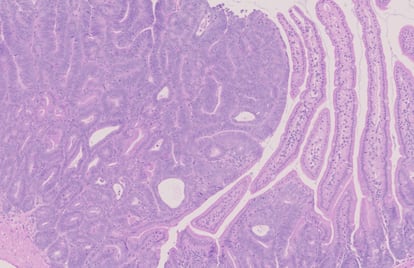

Con la participación de una veintena de instituciones, un amplio grupo de genetistas, oncólogos y veterinarios ha secuenciado 978 genes relacionados con los tumores que tenían este medio centenar de gatos. Son genes con una secuencia y funciones similares a unos mil genes que hay detrás del cáncer en humanos. En conjunto, reunieron tejidos con 13 grandes tipos de cáncer, desde osteosarcoma hasta adenocarcinoma pancreático, pasando por distintos carcinomas mamarios. Procedían de biopsias y necropsias de gatos domésticos, la gran mayoría sin pedigrí, de cinco países.

El cáncer de mama es un buen ejemplo. El estudio identificó siete genes específicos que conducen al desarrollo de ciertos tipos de cánceres mamarios agresivos. El gen impulsor más común es el FBXW7. Más de la mitad de los tumores en gatas presentan mutaciones en este gen. “Un subtipo es el llamado cáncer de mama triple negativo, que es particularmente agresivo y más común en mujeres jóvenes”, destaca Van der Weyden. Los felinos contraen este subtipo de cáncer mamario con mucha mayor frecuencia que los humanos. “En gatos es extremadamente agresivo y se asemeja al cáncer de mama triple negativo en mujeres”, añade la investigadora.